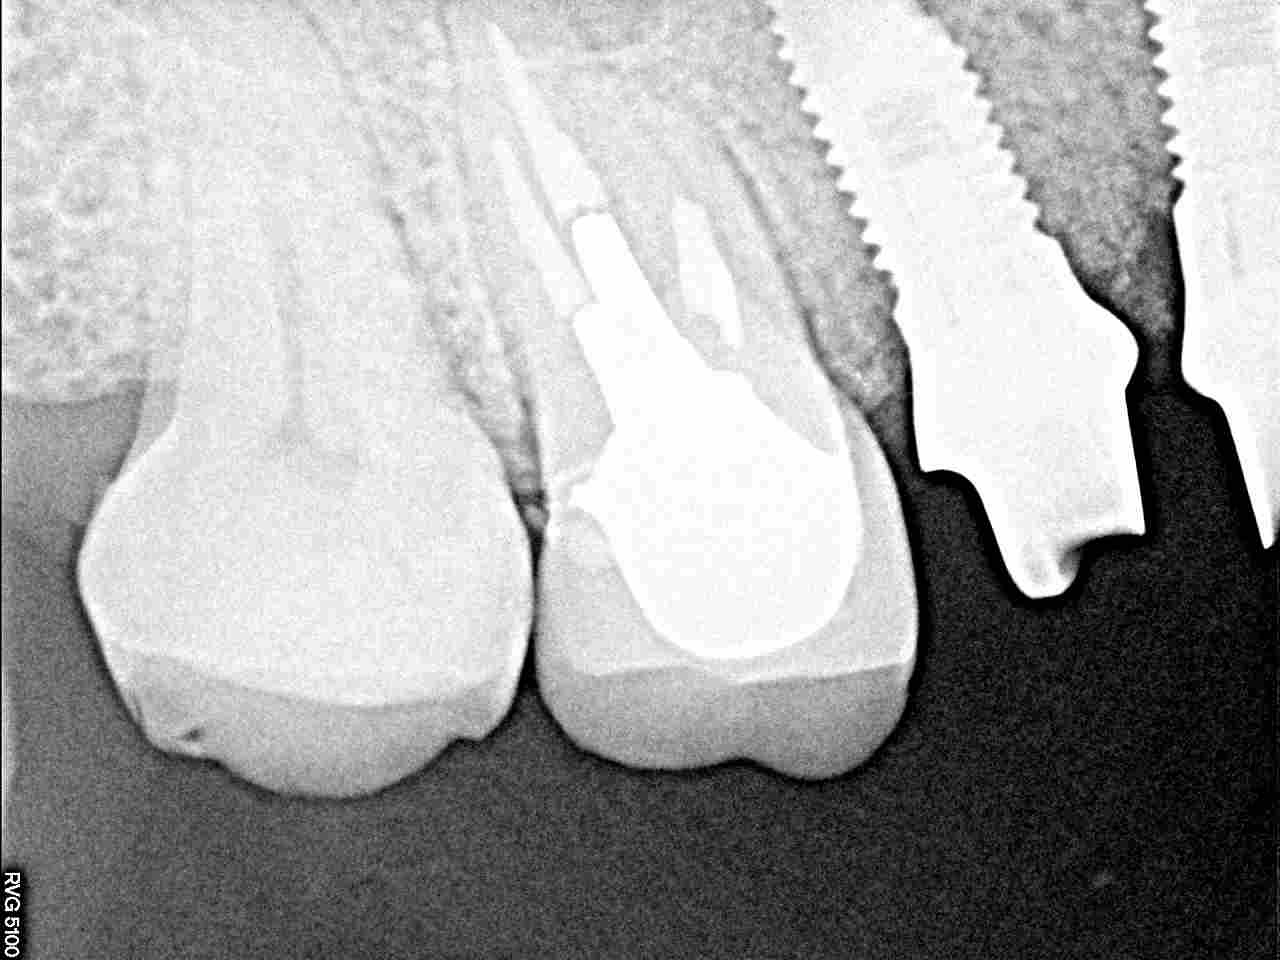

インプラントの最終補綴へ 埋入より3か月後になります|お知らせ |広島市安佐南区の歯科医院 インプラントの最終補綴へ 埋入より3か月後になります トップ お知らせ・ブログ お知らせ インプラントの最終補綴へ 埋入より3か月後になります インプラントの最終補綴へ 埋入より3か月後になります このように傷が治ります きれいに治っています カスタムアバットメントにて作成しています このように立ち上げています レントゲンにてもソーサライゼーションの起こりにくい埋入深さになります オールセラミックにて作成しています 抜歯窩にもドリリング時には足を取られ、上顎洞も持ち上げながら、 スペースが狭くなっていることもあり、5番は少し傾斜埋入となりました Web診療予約 初めての方へ 選ばれ続ける理由 院内設備について 歯が痛いしみる一般歯科 歯がぐらぐらする歯周病 健康な歯を保ちたい予防歯科 子供の虫歯予防をしたい小児歯科 銀歯をセラミックに審美歯科 白い歯を目指しませんか?ホワイトニング 矯正専門医がいるので安心矯正歯科 抜けた歯を補いたいインプラント・入れ歯 医院案内 スタッフ紹介 メリィハウス歯科クリニックオフィシャルホームページ ラベンダー歯科クリニックオフィシャルホームページ お知らせ・ブログ ホーム 診療科目 一般歯科 歯周病治療 予防治療 小児歯科 審美治療 ホワイトニング 矯正歯科 入れ歯・インプラント マウスピース矯正 初めての方へ 院長・スタッフ 設備紹介 医院案内・アクセス メニューを閉じる